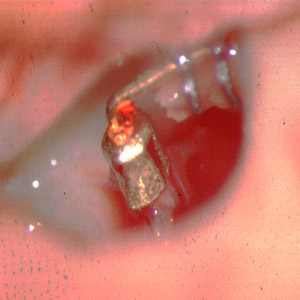

Tympanoplastik Typ 2 - mit einer Winkelprothese wird der Defekt am langen Ambossfortsatz überbrückt.